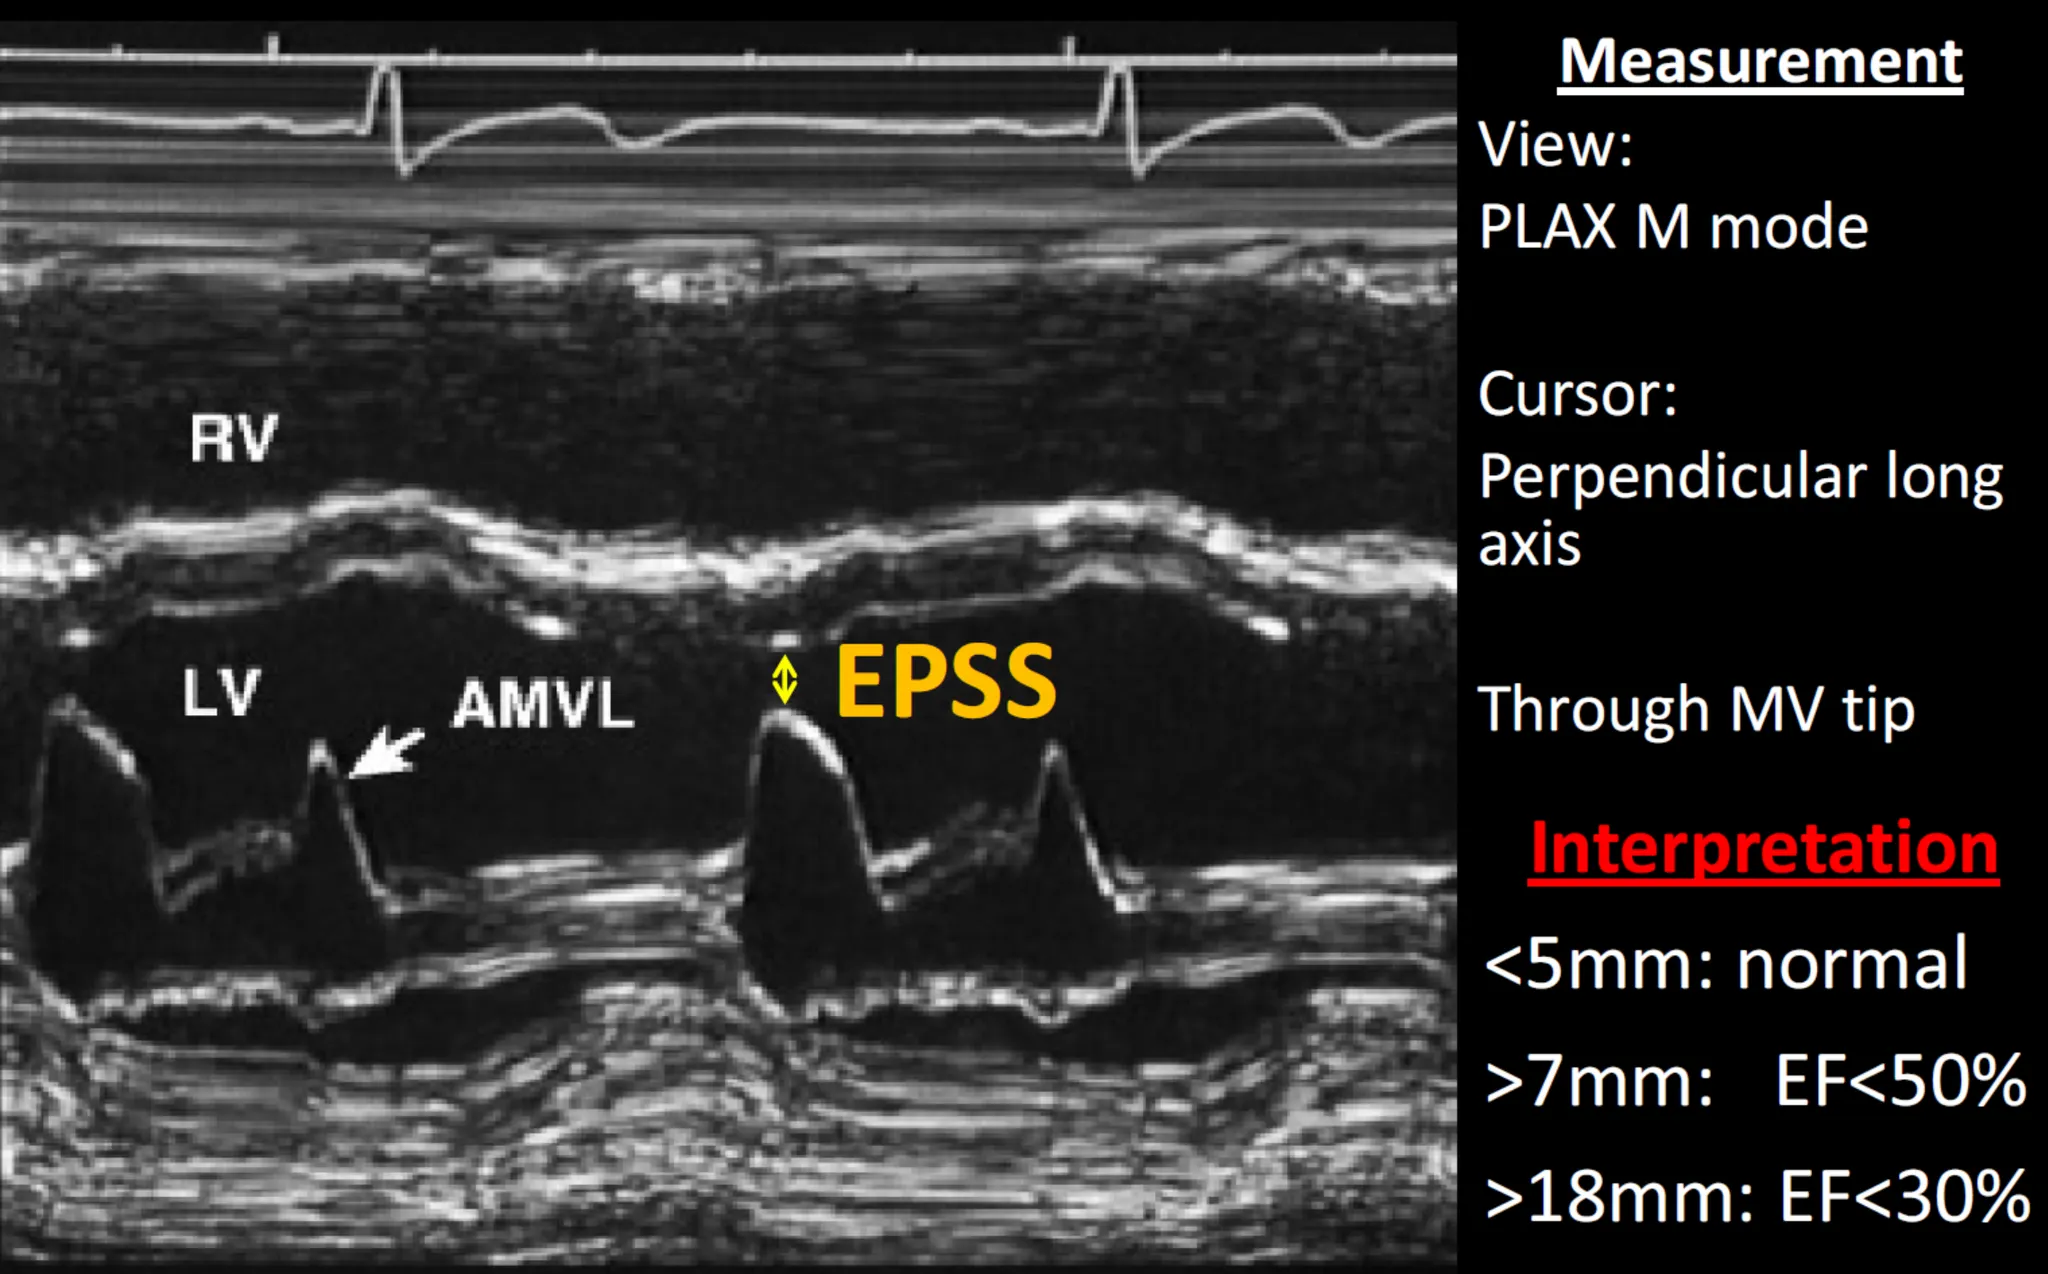

1. E point septal seperation (EPSS)

false positive : MR,MS,AR 시